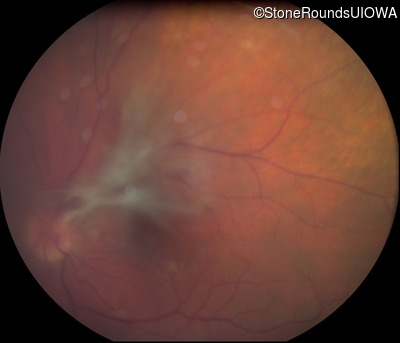

Fundus Photography - Right - 20/20 sc

Exemplar